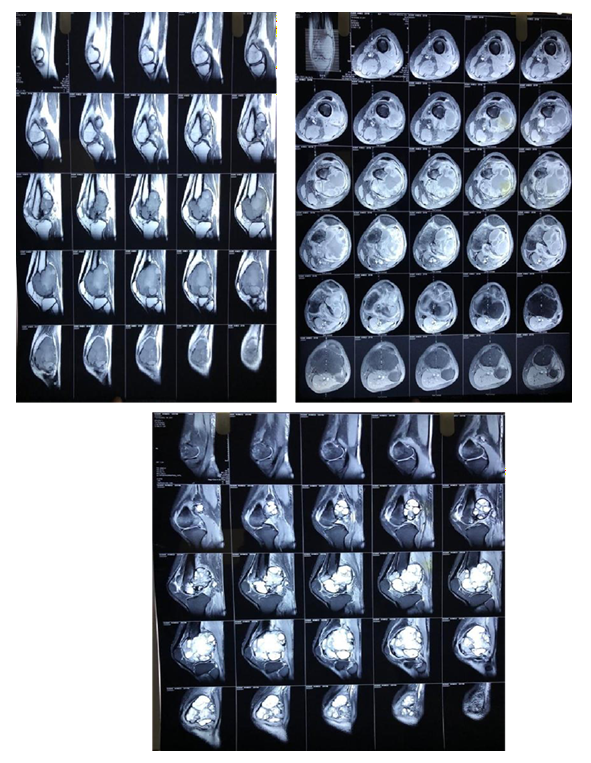

Assessment of Treatment Response

Treatment efficacy and disease status were evaluated by the principal investigator based on a combination of clinical, radiological, and functional parameters. Imaging studies, including X-rays, CT scans, MRI, and ¹8F-fluorodeoxyglucose (FDG) PET scans, were performed periodically to assess tumor size, cortical bone integrity, and soft tissue involvement.²³ Clinical improvement was measured through patient-reported outcomes, including reduction in pain (using the Visual Analog Scale, VAS), improved mobility, and restoration of limb function. Physical examination findings and performance status (Karnofsky Performance Status or ECOG score) were also documented at each follow-up visit.²4Since the study did not mandate a fixed imaging schedule, tumor response was determined holistically by integrating radiological findings, symptomatic relief, and functional recovery, as per the institution’s standard clinical practice.¹7 No predefined standardized criteria (such as RECIST) were enforced, allowing for real-world applicability of the results.

CT scans (detailed assessment of bone integrity and tumor matrix).

MRI (evaluation of soft tissue extension and neurovascular involvement).